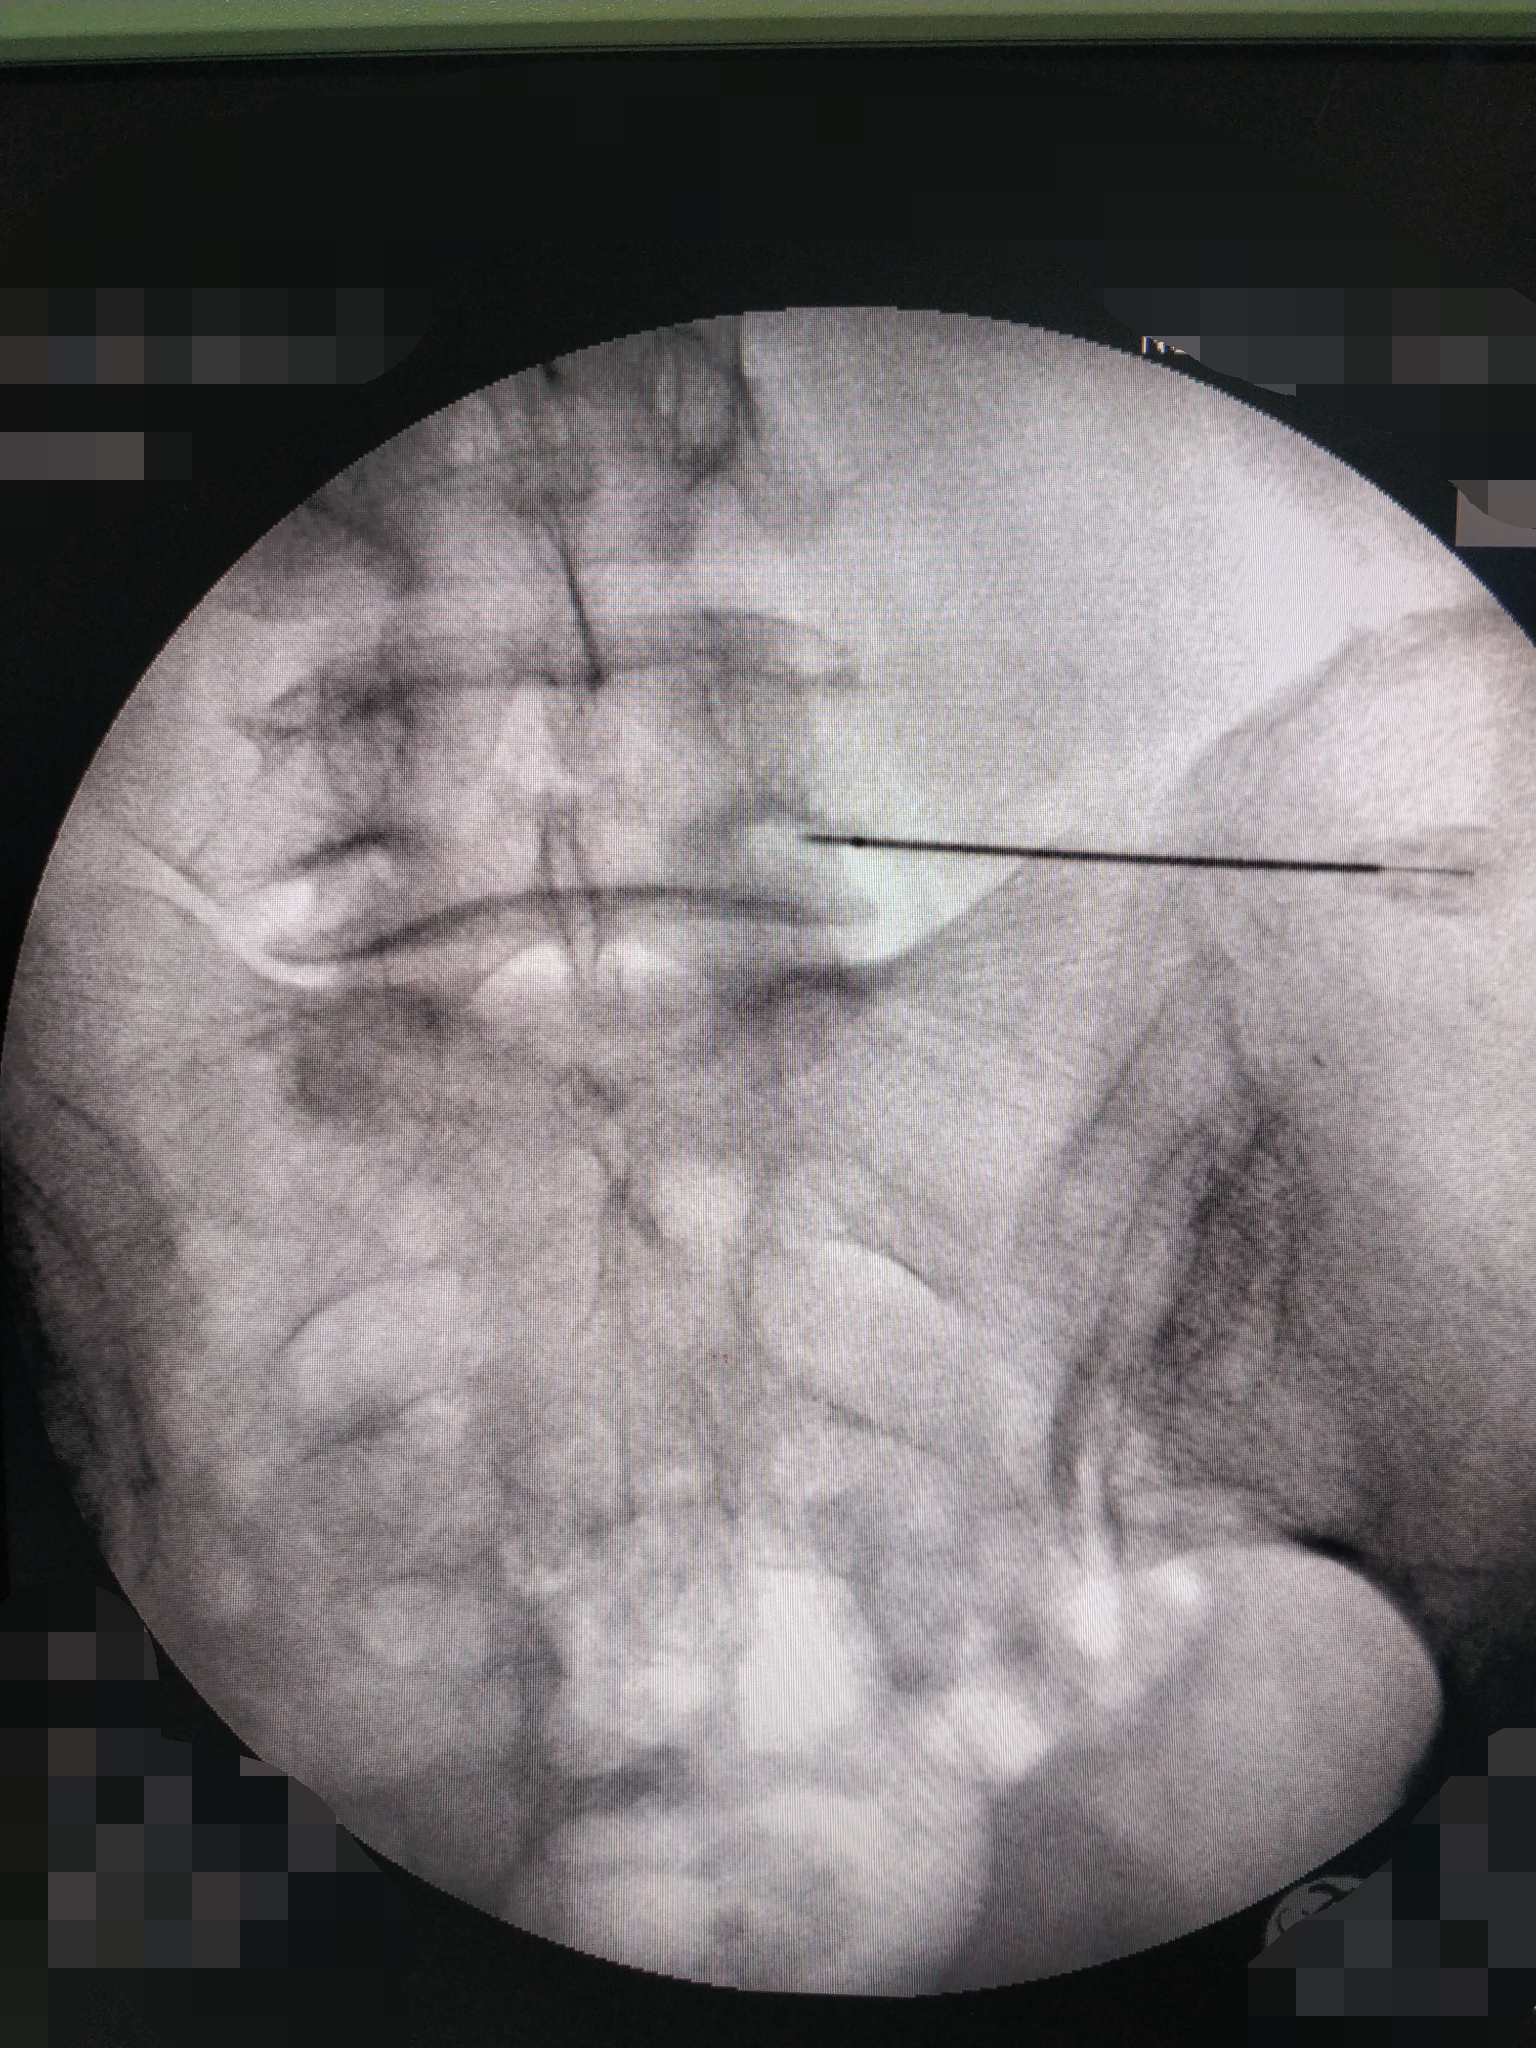

针灸康复科副主任肖祖伟和科室骨干李有超正在DSA下进行射频脉冲治疗

在DSA下的腰椎显像